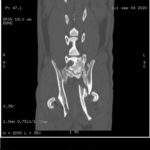

Gracias a vosotros por fin hemos podido realizar el TAC que necesitaba Allan. Os dejamos por aquí algunas de las imágenes y el primer informe emitido por el hospital.

Allan sigue ingresado y tendrá que estarlo varios días más, no sabemos aún cuántos. Deben estabilizarlo y observarlo antes de valorar si es conveniente operarlo. El estado del tórax sigue siendo delicado y tienen que controlar el encharcamiento que tiene en un pulmón. El TAC ha mostrado, además de nuevas fracturas, fracturas anteriores. Es decir, Allan no sólo está así porque recientemente haya recibido un golpe, sino que tiene signos de haber recibido al menos otro golpe anteriormente que también le produjo fracturas, unas fracturas que “se han soldado como han podido”. Como no tenemos ninguna información de Allan hasta la pasada semana que fue cuando recibimos el aviso, no sabemos si antes era capaz de caminar o de hacer caca él solito.